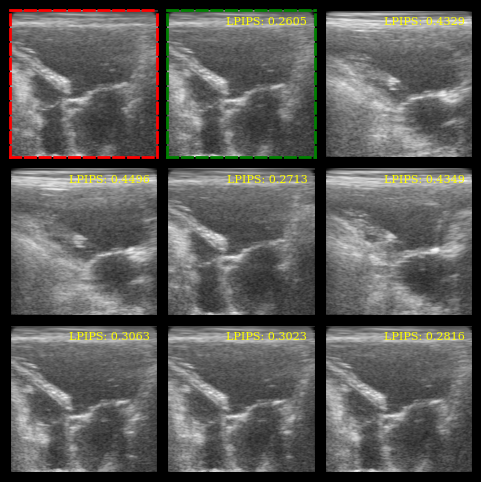

Visualization¶

We plot the images, highlight the reference (red border) and the most similar image (green border), and display the LPIPS scores.

# Red border for reference image

for spine in axes[0].spines.values():

spine.set_edgecolor("red")

spine.set_linewidth(2)

spine.set_linestyle("--")

# Green border for most similar image

most_similar_idx = lpips_scores.argmin()

for spine in axes[most_similar_idx + 1].spines.values():

spine.set_edgecolor("green")

# LPIPS scores as text

for ax, lpips_score in zip(axes[1:], lpips_scores):

ax.text(

0.95,

f"LPIPS: {float(lpips_score):.4f}",

ha="right",

va="top",

transform=ax.transAxes,

fontsize=8,

color="yellow",

)